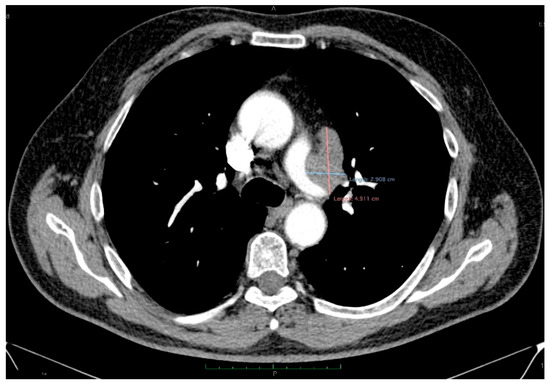

The thoracic contrast-enhanced CT scan provided a para-aortic mediastinal tumor mass with extension into the aortopulmonary window, raising further questions about the nature and origin of the hepatic and cecal lesions. The mediastinal mass was solid, heterogeneous, irregular, lobulated, and exobronchial, measuring 50× 30 × 45 mm. Additionally, lymphadenopathies were identified in the right inferior paratracheal, subcarinal, and paraesophageal regions, as well as adjacent to the left inferior pulmonary vein and the left interlobar area (Figure 5).

Figure 5.

Contrast-enhanced thoracic CT (axial, arterial phase; mediastinal window) demonstrates a lobulated mediastinal mass with heterogeneous enhancement, abutting the right pulmonary artery, measuring approximately 49 × 29 mm in the aortopulmonary window.